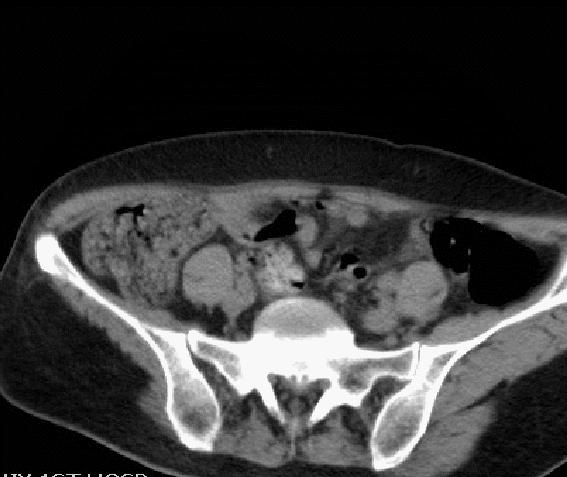

CT 平扫

CT:红色箭头所示为腰3椎体附件包括棘突、双侧椎弓根骨质呈溶骨性破坏, 其内见多发点状、条形骨瘠残留,相应部位见团块状稍低密度影,大小约3.5cmx2cm,边界欠清,密度欠均匀。